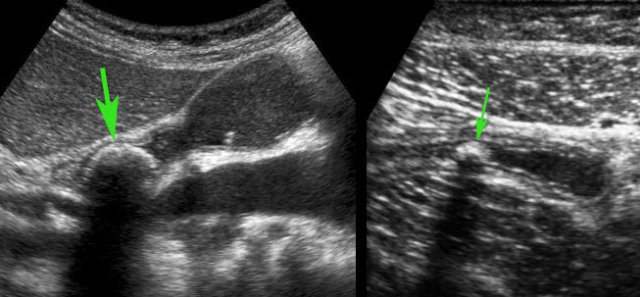

US showed an inflamed appendix (arrow) with an adjacent abscess, walled-off by inflamed fat and the terminal ileum.

There were echolucent connections (*) between the abscess and the ileum, indicating spontaneous evacuation (a and v = right iliac artery and vein).

CT scan confirmed the anatomic situation.

The patient was completely cured with only antibiotics.

Three years later she underwent CT for sigmoid diverticulitis which allowed us to take a look at her appendix region.

The appendix (arrows) was small and still had intimate contact with the ileum (il.)

Another 4 years later, at age 82, she is still doing fine.